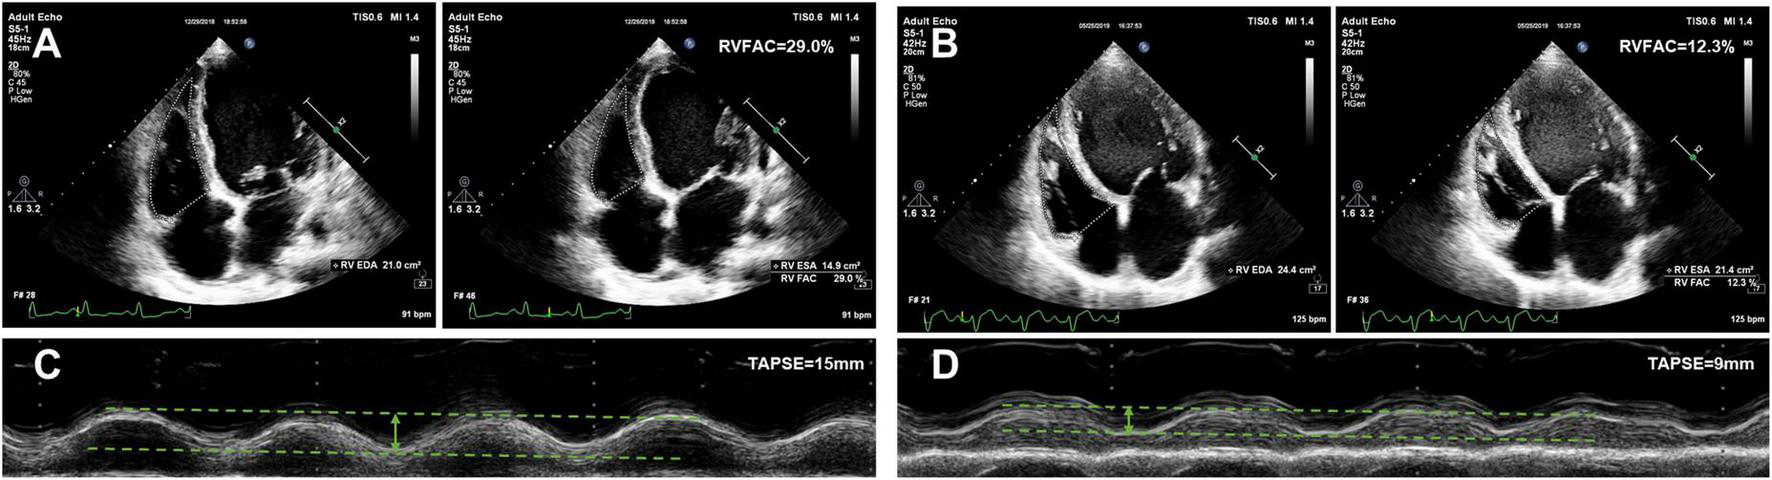

The echocardiographic characteristics according to the AKI stage are given in Table 2. The median time from echocardiographic examination to HTx was 17 days. Patients with a higher AKI stage displayed a larger RA dimension (45, 46, 46, and 55 mm, P trend < 0.001), and a worse RV function (TAPSE 17, 17, 15, and 12 mm, P trend < 0.001; RVFAC 28, 28, 26, and 22%, P trend < 0.001). Representative examples of RVFAC and TAPSE measurement from patients awaiting heart transplant without AKI and with AKI stage 3 are shown in Figure 2. However, left atrial, LV, RV, pulmonary artery (PA), and inferior vena cava (IVC) dimension, LV mass, E/e’ ratio, LV end-diastolic volume, LV end-systolic volume, LVEF, and moderate to severe tricuspid regurgitation did not differ among the AKI stages.

FIGURE 2

Representative examples of RVFAC and TAPSE measurement from patients awaiting heart transplant without AKI and with AKI stage 3. (A) RVFAC in the patient without AKI. (B) RVFAC in the patient with AKI stage 3. (C) TAPSE in the patient without AKI. (D) TAPSE in the patient with AKI stage 3. RVFAC, right ventricular fractional area change; TAPSE, tricuspid annular plane systolic excursion.